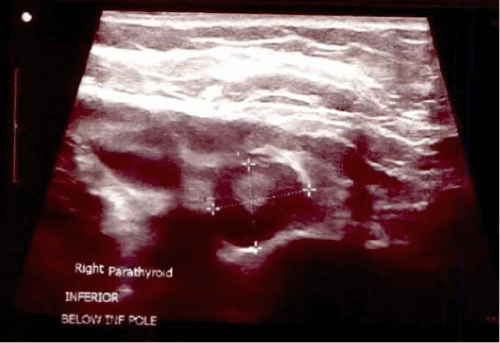

The patient was diagnosed with tertiary hyperparathyroidism due to longstanding secondary hyperparathyroidism. Given her low bone mass and increased bone resorption, alendronate was initiated and slowly titrated up to avoid potential hypocalcemia. Cinacalcet was also prescribed but was never initiated due to cost. After a year of medical therapy, her PTH had worsened (1976 pg/mL), and urine NTx (246 nmol/mmol creatinine) was still elevated. At that point, she was referred to endocrine surgery for her tertiary hyperparathyroidism. Preoperative single-photon emission computed tomography combined with contrast-enhanced CT (SPECT/CECT) imaging demonstrated an enlarged parathyroid inferior to the right thyroid lobe measuring approximately 1.7 × 1.4 × 2.7 cm with focal sestamibi uptake (Figure 1). Surgical clinic ultrasound confirmed the presence of a hypoechoic structure in the corresponding location, which appeared to potentially be two abutting right-sided parathyroid glands (Figure 2). Our clinical practice is to routinely perform preoperative SPECT hybridization with contrast-enhanced CT scanning (SPECT/CECT) to aid in identifying and localizing any ectopic parathyroid glands. We additionally routinely perform an in-office ultrasound to aid in preoperative parathyroid gland localization and rule out concomitant thyroid pathology before taking a patient to the operating room.

Figure 2. Surgical Clinic Ultrasound Findings. A) Right Superior Parathyroid and B) Right Inferior Parathyroid. Published with Permission

A.

B.